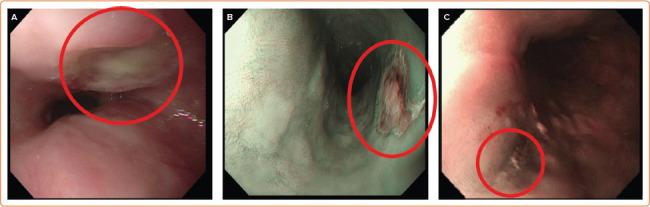

Injury to structures adjacent to the heart, particularly oesophageal injury, accounts for a large proportion of fatal and life-altering complications of ablation for persistent AF. Avoiding these complications dictates many aspects of the way ablation is performed. Because avoidance involves limiting energy delivery in areas of interest, fear of extracardiac injury can impede the ability of the operator to perform an effective procedure. New techniques are becoming available that may permit the operator to circumvent this dilemma and deliver effective ablation with less risk to adjacent structures. The authors review all methods available to avoid injury to extracardiac structures to put these developments in context.

心脏邻近结构的损伤,尤其是食管损伤,在持续性房颤消融的致命和改变生活的并发症中占很大比例。避免这些并发症决定了消融手术的许多方面。由于避免措施涉及限制在感兴趣区域的能量传递,对心外损伤的担忧可能会妨碍操作者进行有效手术的能力。新的技术正在出现,这可能使操作者能够规避这一困境,并在降低对邻近结构风险的情况下进行有效的消融。作者回顾了所有可用于避免心外结构损伤的方法,以便将这些进展置于相应背景中。